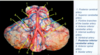

Which arteries do the arrows point to? [1]

Lenticulostiate arteries